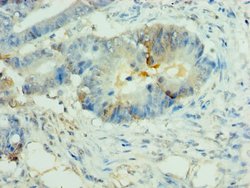

NALP2 Polyclonal Antibody for Western Blot, IHC (P), ELISA

| ELISA, Immunohistochemistry (Paraffin), Western Blot | |